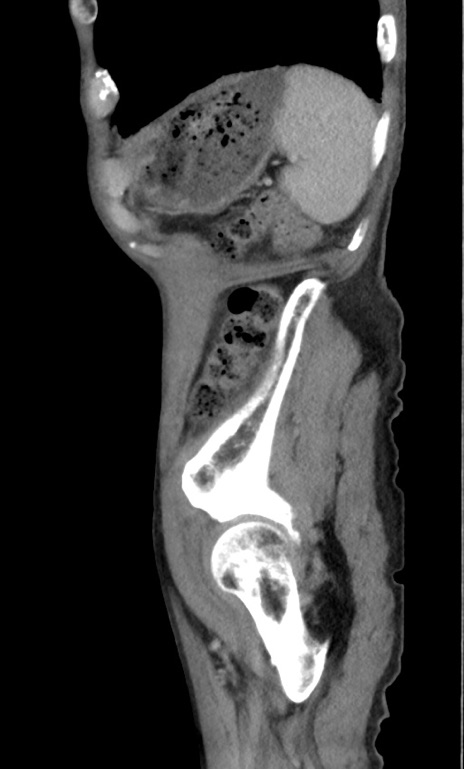

症例3(矢状断像)

【症例】 70歳代男性

【主訴】右鼠径部腫瘤、疼痛

【現病歴】本日朝より上記主訴あり、受診。

【既往歴】膀胱癌にて膀胱全摘、両側尿管皮膚瘻

【データ】WBC 5600、CRP 0.56